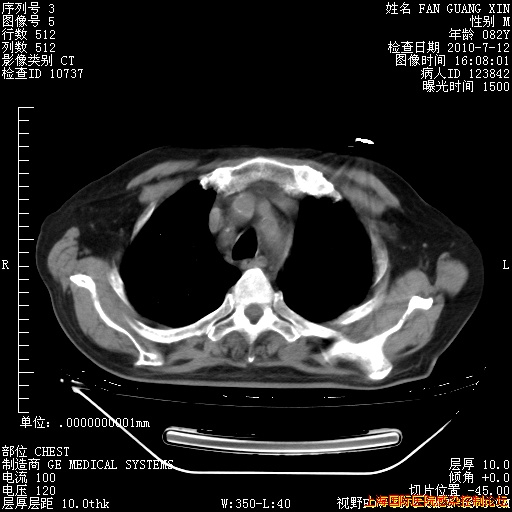

补发6月12日肺部CT肺窗

6月12日肺窗

6月12日纵膈窗